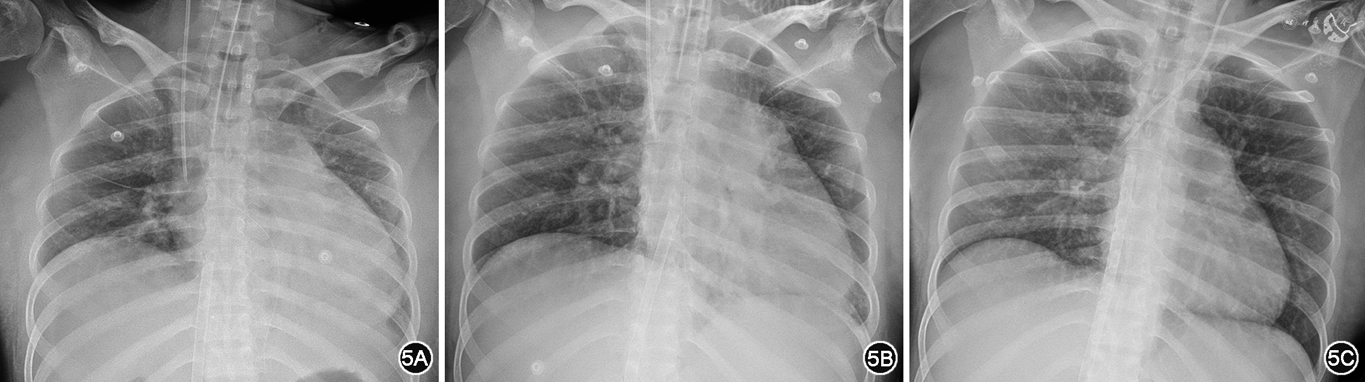

经上述积极治疗后患者病情逐渐好转,神志清晰,生命体征稳定,高敏肌钙蛋白I及NT-proBNP逐渐回落至正常(图4),床旁胸片提示心脏逐渐缩小(图5),超声心动图提示右心室逐渐缩小,左心室舒张末期内径逐渐增大,估测肺动脉收缩压明显下降(表1),补体C3恢复正常(表2),脑脊液蛋白降至0.77 g/L,于4月7日拔除气管插管,于4月19日撤离ECMO,4月22日停用所有血管活性药物,患者循环稳定,系统性红斑狼疮病情缓解,一般情况可,5月16日带药出院。病例报告内容已获患者知情同意。